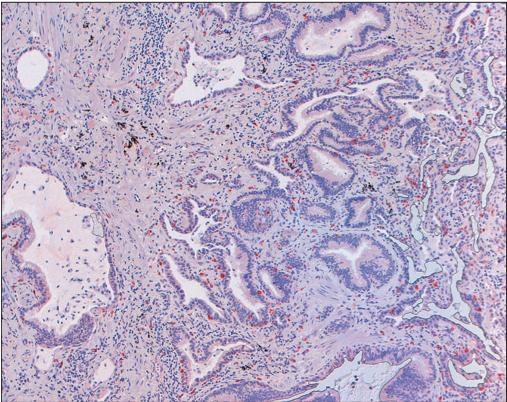

RA所致肺间质病变的活检表现